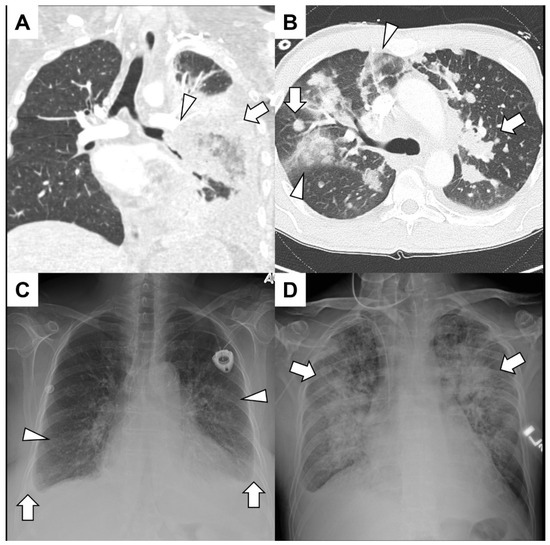

5.1. Primary Lung Cancer

5.2. Pulmonary Metastasis

- For stabilized/nonmassive cases, a CT chest scan should be obtained. Subsequent bronchoscopy may be considered for local thermoablative therapies, such as electrocautery, argon plasma coagulation, or Nd:YAG laser, especially for hemoptysis from malignant central airway disease [70]. In those cases not amenable to tracheobronchial intervention, definitive therapeutic interventions, such as bronchial artery embolization (BAE) or surgery may be warranted [69,70].